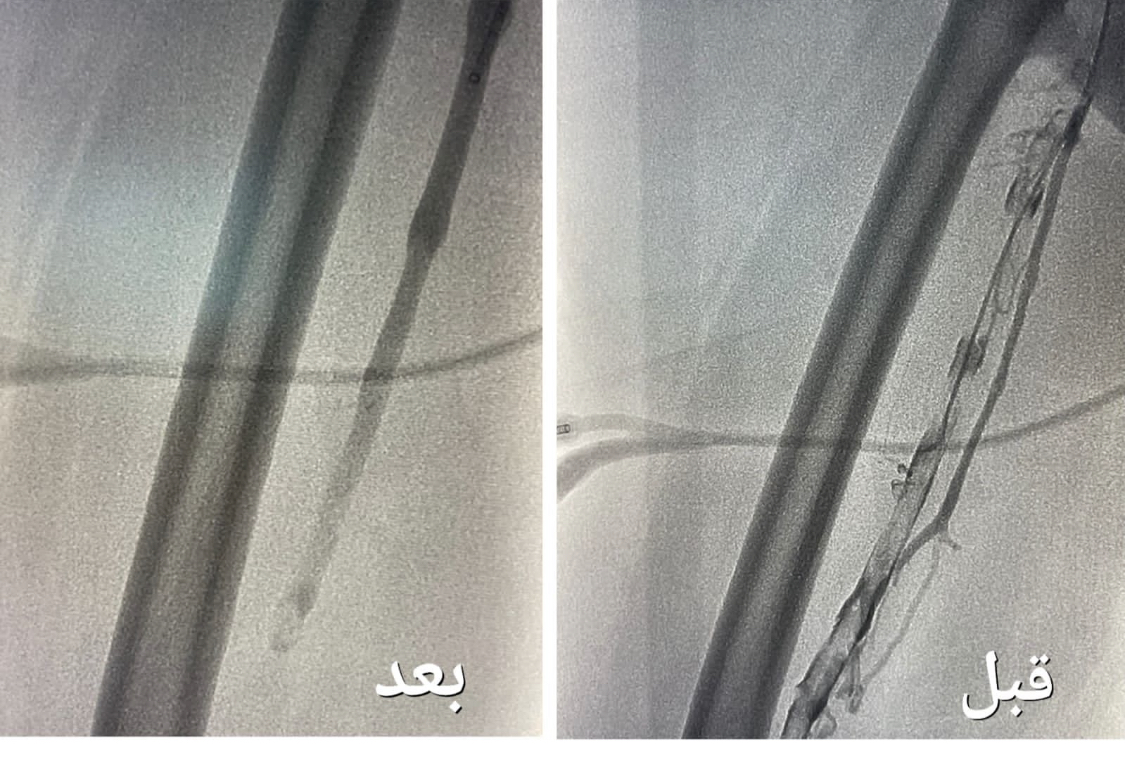

وأوضحت “الصحة” أنه بعد إجراء الفحوصات الطبية و الكشف تبين وجود جلطة وريدية من مستوى الكاحل إلى مستوى أوردة الحوض الأيمن ، و انسداد كامل في أوردة القدم اليمنى حتى الحوض ، قرر بعدها الفريق الطبي تنويم المريضة و التنسيق مع فريق وحدة الأشعة التداخلية بشكل عاجل لدراسة الحالة و معالجتها ، و وضع الخطة العلاجية ، لنقلها إلى غرف عمليات الأشعة لإجراء عملية بإستخدام جهاز إزالة الجلطات تحت التخدير الموضعي و التهدئة الواعية .

وقالت الوزارة إن العملية

استغرقت نحو ساعتين ، تكللت _ ولله الحمد_ بالنجاح ، تم فيها تركيب فلتر للوريد الأجوف السفلي لمنع انتقال الجلطات للرئة ، و من ثم الدخول للوريد المتجلط في مستوى الكاحل و حقن مواد مذيبة للجلطات ، و قد أستخدمت اجهزة نوعيه لمثل هذه الحالات والتي تعمل على سحب الجلطات بعد إذابتها و توسعة الأوردة بالبالون لإعادة جريان الدم .